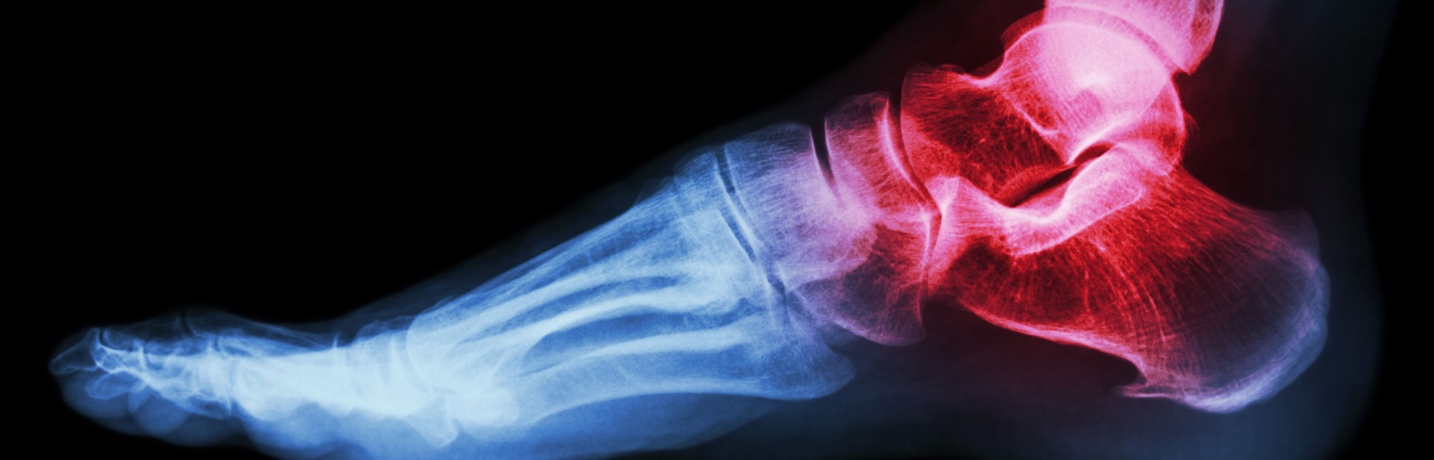

Les chevilles supportent tout le poids du corps lorsque nous marchons, sommes debout ou courons. Parce que l’articulation de la cheville, relativement petite, supporte tant de poids, elle devient au fil du temps particulièrement vulnérable aux blessures et à la détérioration. Les blessures à la cheville peuvent prédisposer à l’arthrose. Les personnes atteintes de polyarthrite rhumatoïde peuvent également présenter de la douleur et de l’inflammation chroniques à une cheville ou aux deux.